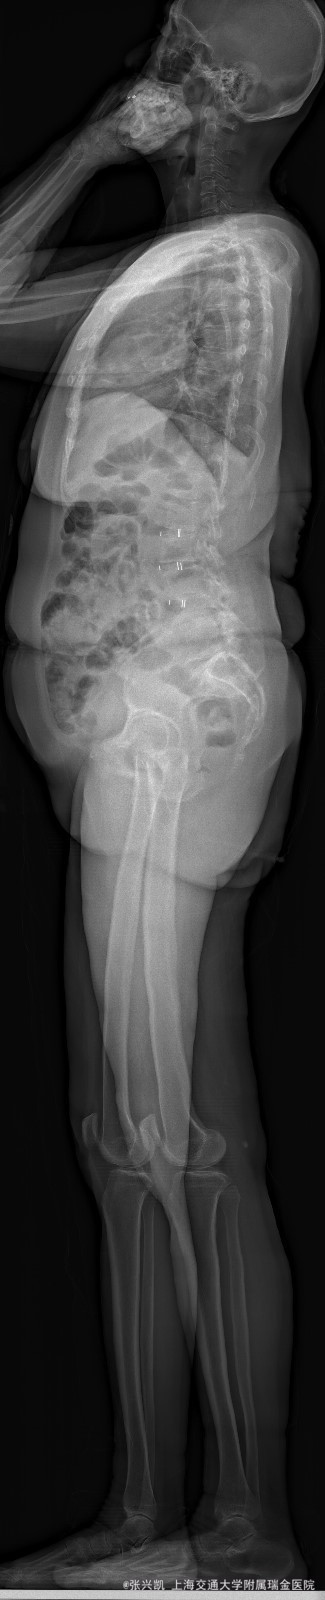

主诉:双下肢麻木7年,腰部酸痛无力 现病史:女性患者,70岁,患者诉腰背无力十几年,约于7年前无明显诱因下出现下肢麻木,站立位加重。后出现腰臀部僵硬,弓背加重,行走距离较短, 不足百米,几年前外院检查诊断为腰椎管狭窄,具体不详。

查体:侧弯畸形,右臀部及右下肢麻木疼痛,腰部活动受限,难以站立。右侧支腿抬高试验50°。双下肢肌力肌张力可。 辅助检查: 磁共振:L1-5,L5-S1腰椎椎间盘突出,腰椎退变,腰椎侧弯

诊断: 腰椎侧弯,腰椎间盘突出 治疗:1期微创侧路椎体融合术+2期 微创后路经皮内固定术

患者侧路微创术后神经压迫症状减轻,腰椎矢状位及冠状位腰椎力线得到改善,戴支具术后可早期下床活动,术后2周后行后路固定手术。